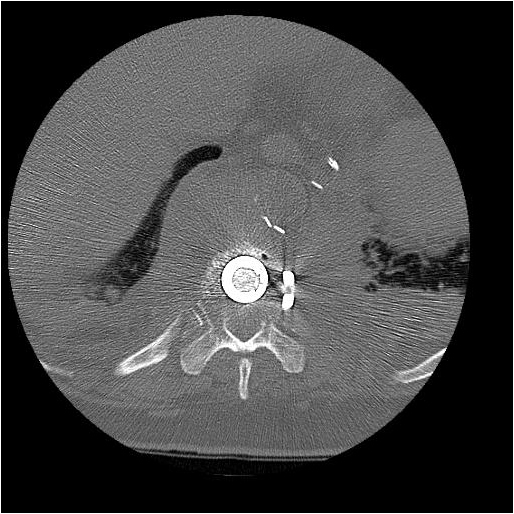

After completion of the spinal procedure, reorientation of the thoracic surgeon by the spinal surgeon is performed, including visualization of the implanted hardware and an explanation of the procedure that was performed (Figures 9a-c). Hemostasis is secured, the chest irrigated, and the posterior mediastinum is inspected for lymph leak (the presence of a CSF leak must be ruled out by the spine surgeon prior to this point in the operation). The diaphragm, if mobilized, is reattached to the fascia of the posterior chest wall with interrupted horizontal 0 prolene sutures or is anchored around the rib. A 28 Fr chest tube is placed in the posterior mediastinum and the chest is closed in a standard fashion. Postoperative spine imaging is necessary to demonstrate adequate position of the hardware and correction of the vertebral defect (Figures 10a-e, Video).

| Figure 9a: Resected vertebral body | Figure 9b: Prosthetic vertebral body placement | Figure 9c: Vertebral fixation plate |

| Figure 10a-e: CT of spine after fixation | Figure 10b | Figure 10c |

| Figure 10d | Figure 10e |